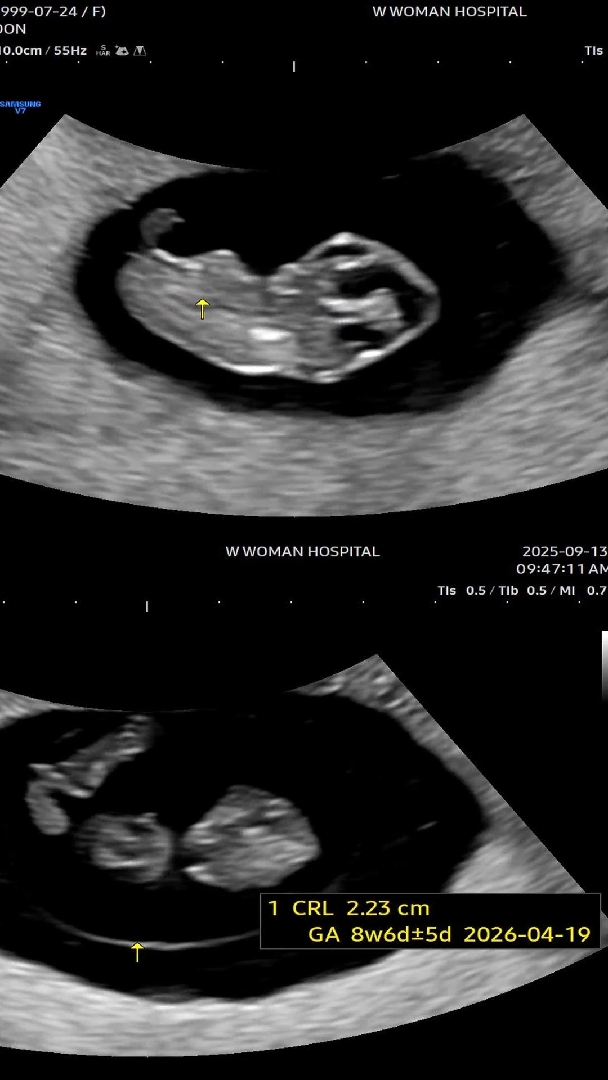

9주차 초음파🐢

오늘 주수 정정되었어요! 9주 1일 -> 8주 6일 아가 : 2.23cm 심박수 : 184bpm 오늘은 손도 흔들어주고🥹👋 앙증맞은 두 다리도 보여줘서 초음파 보는 내내 남편이랑 귀엽다는 말만 계속 했어요 ㅋㅋㅋ 코도 괜히 높아보여서 도치맘 예약입니둥...